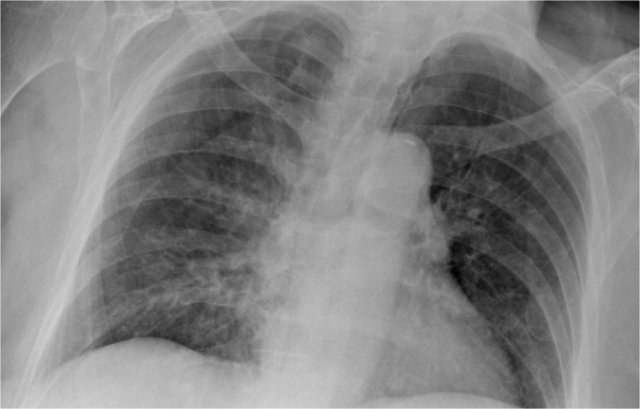

First study the CXR.

We know that in some cases there is an extra joint in the anterior part of the first rib which may simulate a mass.

However this is also a hidden area where it can be difficult to detect a mass.

In this case a small lung cancer is seen behind the left first rib.

Notice that is is also seen on the lateral view in the retrosternal area.

Continue with the PET-CT.

The PET-CT demonstrates the tumor (arrow) which has already spread to the bone and liver.

The diagnosis was made by a biopsy of an osteeolytic metastasis in the iliac bone.